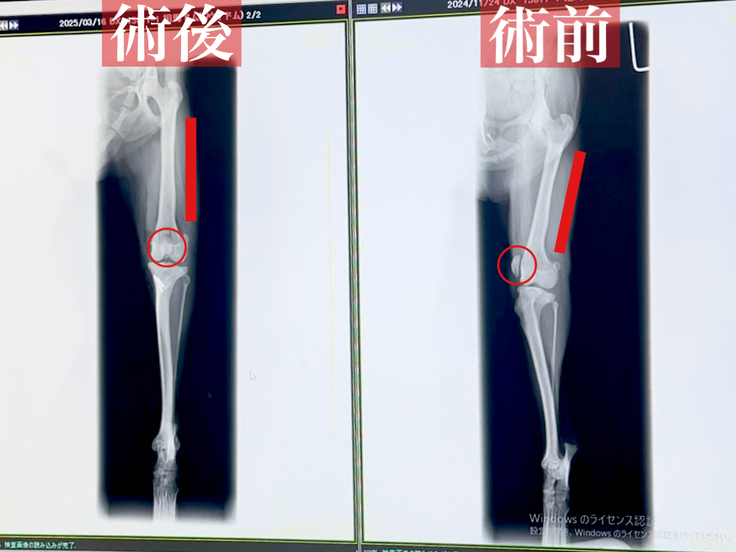

ドムの手術についてのご説明です。

ドムが今回受けた手術は

⚫︎脛骨粗面転位術 ⚫︎外側支帯の縫縮

⚫︎滑車溝形成術(ブロック状造溝術)です。

手術前は膝のお皿が大きく外れています。

手術後はしっかりとお皿の位置が正常に戻り、曲がっていた骨も真っ直ぐと矯正されていました。

骨が歪んでいたので切断し2本のピンで固定しています。